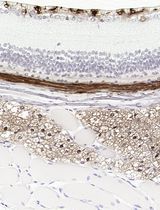

(Optional) Take 10,000-50,000 cells for RNA extraction to do quality controls on the samples. RNA can be isolated using standard column kits. After cDNA generation (following the manufacturer’s specifications), each sample should be checked for its Col2a1/Col1a1 ratio, and in the case of OA cartilage, for Mmp 3, 9, and 13 expression using quantitative real-time PCR (qPCR). Relative expression can be calculated using the standard delta delta CT method (Livak and Schmittgen, 2001). To ensure samples are not dedifferentiated, the ratio of Col2a1/Col1a Ct values should be >1, although the exact ratio for each sample will vary. In our hands, Mmp expression is anywhere between 10-10,000 fold higher in OA cartilage than in healthy cartilage (Figure 2A).

Figure 2. Quality control for cartilage samples and cyTOF data. A. Representative values of MMP3, MMP9, and MMP13 expression from 5 healthy (blue) and 20 OA cartilage samples (black). The values plotted are normalized with actin as a housekeeping gene and relative to one normal cartilage sample. Col2a1 and Col1a1 expression is shown as a ratio. All samples retaining a chondrogenic phenotype should have a Col2a1/Col1a1 ratio >1. Data is re-analyzed from the same patients as in Grandi et al. (2020). B. EU control bead signal before and after run time normalization. This can help to normalize samples internally (over the run time) and between runs, as shown here. C. Dot plot of two healthy cartilage samples, showing expression of SOX9 and CD44, as measured by cyTOF. Expression on each axis is arcsine transformed, and a representative gate is shown, although this will vary with the signal-to-noise ratio of each run. On the left is an example of a high-quality sample where >74% of the live-cell (i.e., cisplatin negative) events have staining for both SOX9 and CD44. On the right is an example of a low-quality sample that was not included in downstream analyses, where <2% of the live cell events were inside the SOX9/CD44 gate. D. A histogram of SOX9 cell expression is plotted for the same cartilage sample profiled on two different temporarily separated batches (orange and blue). The left graph depicts the samples before normalization; note that, while the sample is exactly from the same patient, the intensities look different. The graph on the right depicts the same set of samples but after normalization, when staining intensities are comparable.